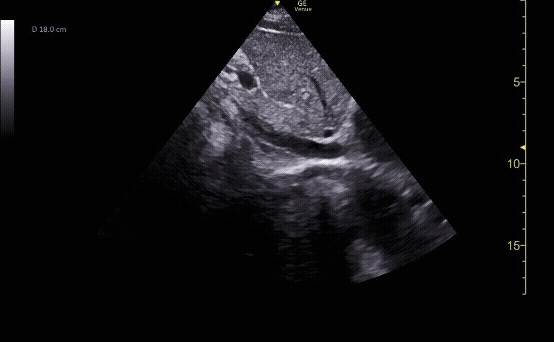

Subxiphoid view showing the liver, right ventricle, right atrium, left atrium, and left ventricle.

c/o Kyle Ackerman, MD